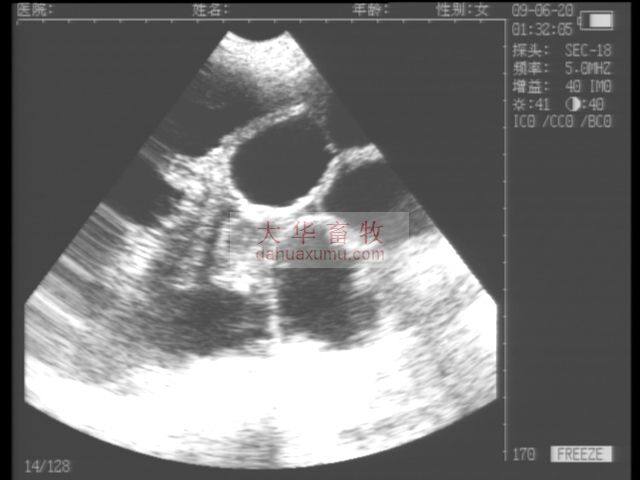

适用于猪等动物怀孕诊断

高性价比,能出色的胜任猪场等的怀孕检测等工作。

探 头:3.5MHz防水机械扇扫(可选配5.0MHZ防水机械扇扫)

独特的小型防水机械扇扫探头,既可作为常规体外探头,也可作为直肠探头使用

探头频率可调节,应用范围更广